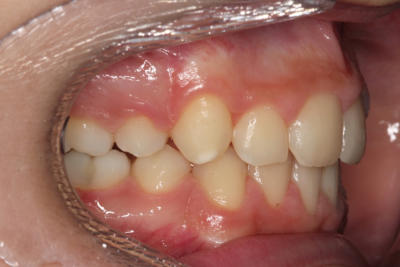

Crowding – Child case